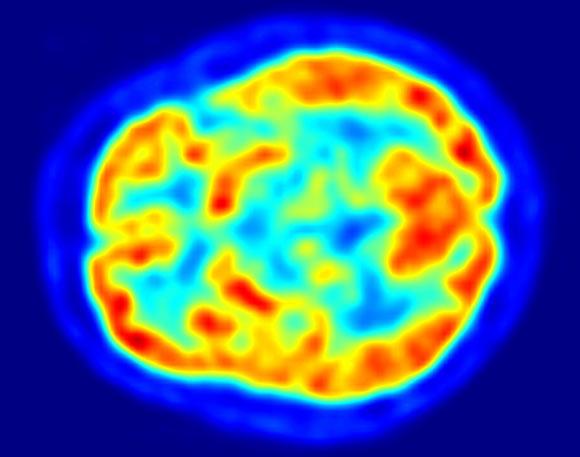

Researchers mapped brain activity when volunteers read poetry and prose. The results show that poetry is like music to the human mind. Image credit: Jens Langner. Οι ερευνητές χαρτογραφούσαν την εγκεφαλική δραστηριότητα όταν οι εθελοντές διαβάζουν ποίηση και πεζογραφία. Τα αποτελέσματα δείχνουν ότι η ποίηση είναι σαν τη μουσική στο ανθρώπινο μυαλό.

Η σχέση της δημιουργικότητας με την συνειδητότητα είναι προφανής καθ όσον Όλες οι καλλιτεχνικές δραστηριότητες είναι αποτέλεσμα της δημιουργικότητας, που μπορεί να γίνει αντιληπτή ως πράξη μη τοπικής ,αλλα στιγμιαίας αλληλεπίδρασης με ένα άλλο πεδίο της πραγματικότητας .ο Βerkmen μας λέει ότι οι πληροφορίες μπορούν να φθασουν μέχρι εμάς σαν strings,άυλες χορδές, ινες, σαν να περνούν από τούνελ, και μπορούν να γίνουν αντιληπτές στιγμιαία, γρηγορότερα από την ταχύτητα του φωτός. Έτσι, «η δημιουργικότητα μπορεί να γίνει κατανοητή ως πράξη μη τοπικής στιγμιαίας αλληλεπίδρασης με ένα άλλο πεδίο της πραγματικότητας» (Η.Berkmen 2017)Αλλά πως η δημιουργικότητα σχετίζεται με την Neuroscience,ερευνες αποδεικνύουν ότι όταν τα ατομα βρίσκονται κατω από την επήρεια δημιουργικής διαδικασίας (μουσική,τραγούδι,ζωγραφική,ποίηση,η κάθε άλλη διαδικασία έκφρασης),ο εγκέφαλος είναι σαν να βρίσκεται σε πάρτυ με πυροτεχνήματα,μια πληθώρα περιοχών του φωτιζεται, και τρομερά πολύπλοκες νευρικες διαδικασίες συμβαίνουν αυτόματα ,καθως ανταλασσονται πληροφορίες μεταξυ των δυο ημισφαιριων του εγκεφαλου με ένα αξιοθαύμαστο τρόπο( Bolwerk A.2014 “How Art Changes Your Brain”. ,Limb,Braun, 2008 “Neural substrates of spontaneous musical performance” )